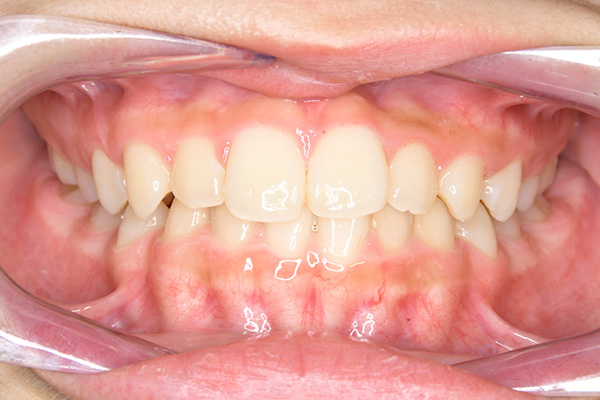

動的治療終了時

FP・IOP